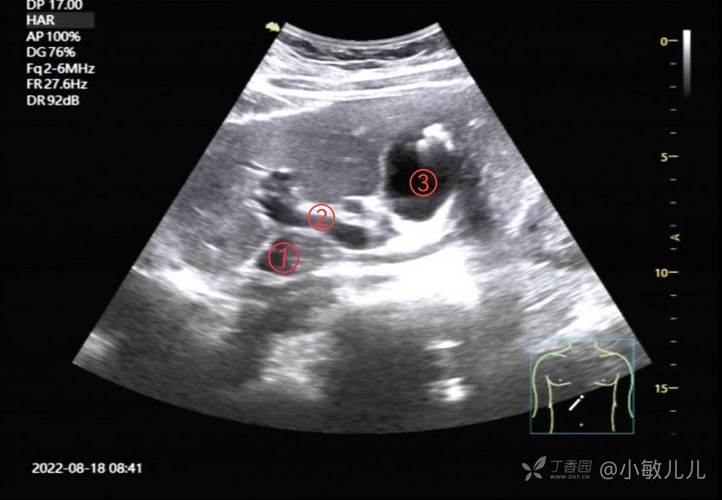

超声波属于机械波,人耳听不到,其频率超过20000赫兹,医学超声检查常用频率为2.5-10兆赫兹,腹部检查多选用3.5-5兆赫兹的探头,既能穿透较厚的腹壁组织,又能保证足够的图像分辨率,检查时,患者需暴露腹部,医生在探头涂抹耦合剂(排除空气干扰,确保声波传导),通过不同切面移动探头,实时观察脏器回声特征,肝脏实质呈均匀低回声,胆囊为无回声的囊性结构,而结石或肿瘤则表现为强回声或混杂回声团块,彩色多普勒超声还可叠加显示脏器及病灶内的血流信号,帮助鉴别囊实性病变、评估血管狭窄或肿瘤血供情况。

- 肝脏系统:可检测脂肪肝、肝硬化、肝囊肿、肝血管瘤、肝癌等,通过测量肝右叶斜径、前后径及门静脉内径,评估肝脏大小及门脉压力;对早期肝癌的检出率较高,尤其对于合并慢性肝病的高危人群,是常规筛查项目。

- 胆囊与胆道:对胆囊结石、胆囊炎、胆囊息肉、胆总管扩张等具有诊断价值,尤其擅长显示X线阴性的胆固醇结石和胆泥淤积。

- 胰腺:因胰腺位置较深,易受肠道气体干扰,但经验丰富的医生仍可观察胰腺形态、边缘及回声,诊断胰腺炎、胰腺囊肿、胰腺癌等疾病,必要时需结合增强CT或MRI。

- 脾脏:用于评估脾脏大小(脾脏厚度正常<4cm),检测脾脏梗死、血管瘤、淋巴瘤等病变,对肝硬化伴脾功能亢进的诊断有重要意义。

- 泌尿系统:可观察肾脏大小、皮质回声,诊断肾囊肿、肾结石、肾积水、肾肿瘤等;同时检查膀胱充盈情况,发现膀胱结石、肿瘤或前列腺增生(经腹壁超声可测量前列腺体积)。